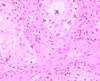

Case presentation: A case of burned-out tumor of the testis in a 31-year-old man is reported. The tumor presented as a retroperitoneal mass with histological characteristic of a seminoma. The testes on clinical examination were normal, and a suspicious lesion in the scrotum was only identified after ultrasound. Incision of the abdominal mass was decided, followed by orchectomy. Histological examination of the testis revealed a suspicious lesion with characteristics of spontaneous regression of germ cell tumors.

Conclusion: We describe one of very few cases worldwide, where spontaneous regression of a primary testicular tumor occurred after demonstration of retroperitoneal lymph node metastasis, a phenomenon known as burned-out seminoma, which is hard to recognize and incompletely characterized by physicians.